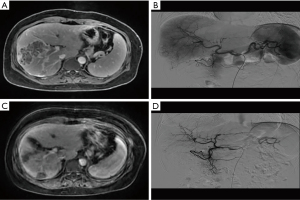

Safety

AEs were similar in both groups, with most patients having hand-foot reactions (≤ grade 2). Three patients in the PD-1 group had hypertension (grade 2), one patient experienced decreased weight (grade 2), and another had proteinuria (grade 2). In the continued TACE–regorafenib group three patients had hypertension (grade 2), one experienced decreased weight (grade 1), and one patient had diarrhea (grade 2) (Table 3). One patient in the PD-1 group died of immune hepatitis after 3 months of therapy (Figure 4).

The safety of regorafenib combined with sintilimab was generally consistent with historical data (16). AEs were also low and similar between the two groups in our study. This may be because the doses of sorafenib and regorafenib used in our study were relatively small. However, one patient in the PD-1 group died of immune hepatitis after 3 months of therapy. The patient exhibited a huge tumor burden (Figure 4), and after TACE combined with regorafenib and sintilimab, the immune hepatitis and rapid deterioration of liver function led to their death.